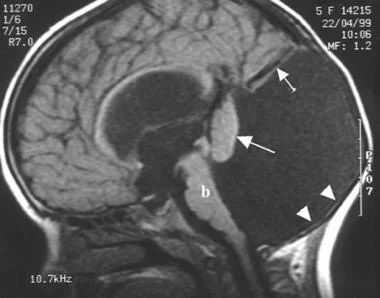

Аномалия Арнольда-Киари на МРТ (магнитно-резонансных томограммах). Видно, что при аномалии Арнольда-Киари мозжечок смещен вниз и подобно пробке вклинен в позвоночный канал.

Диагноз аномалии Арнольда-Киари нетрудно установить с помощью МР-томографии головного мозга или МРТ шейного отдела позвоночника. При необходимости мы используем рентгеновскую компьютерную томографию с трехмерной реконструкцией затылочной кости и шейных позвонков.